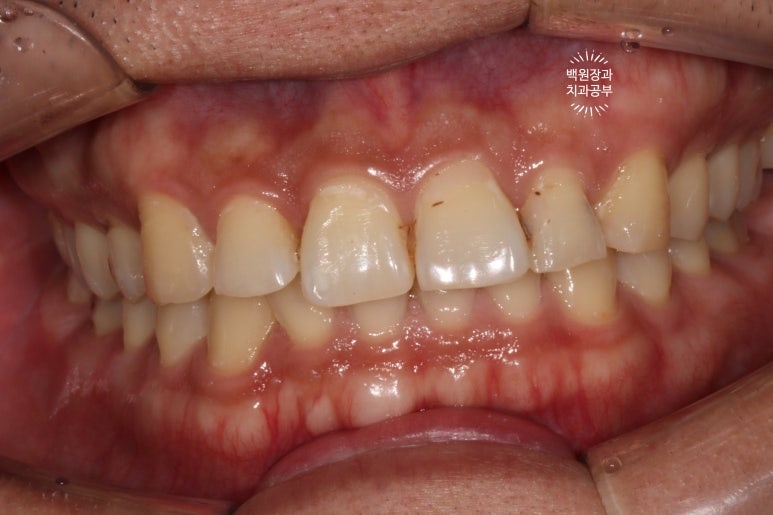

앞니에 레진 치료를 이미 받으셨던 환자분이셨습니다.

정면으로 보이는 곳은 기존 레진의 변색으로 인한 discoloration이 관찰되었고,

위턱 앞니 중 왼쪽 치아들은 옆면에 충치 (치아우식증)가 아주 선명히 보이고 있네요.